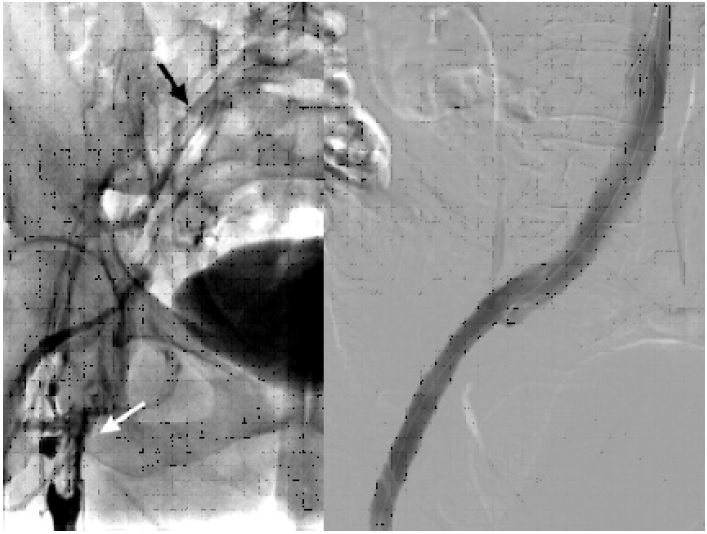

Mujer de 55 años, previamente sana, que consulta por cuadro de edema marcado de todo el miembro inferior izquierdo, con dolor incapacitante, coloración azulada-violácea del miembro y parestesias en el pie, que comenzó una semana previa a la consulta y que fue empeorando al punto de inhabilitar la marcha. Al examen físico era notable el edema desde el pie hasta la raíz del muslo, tenso, así como la ausencia de pulsos distales con solo señales monofásicas por Doppler sin alteración de la función motora. El eco Doppler reveló una TVP que involucraba las venas femoral común, femoral proximal y femoral profunda, y también la vena safena magna, por lo que se decidió iniciar de inmediato anticoagulación con heparina de bajo peso molecular. La angiotomografía mostró una extensa TVP desde la vena ilíaca externa izquierda proximal hasta la vena poplítea, al igual que una bifurcación aórtica retrocava, con compresión a nivel de la confluencia de las venas ilíacas externa e interna, entre el sacro y la arteria hipogástrica izquierda (Figura 1).

Se decidió llevar a la paciente a Hemodinamia para colocación de un filtro de vena cava inferior (VCI) por vía femoral derecha. Luego, con la paciente en decúbito ventral, se realizó una punción guiada por ecografía de la vena poplítea con colocación de un introductor 11 French por medio del cual se llevó a cabo una trombectomía mecánica de toda la oclusión con dispositivo Aspirex®S. Un claro sitio de compresión se notó al mismo nivel observado en la angiotomografía, que ocasionaba incluso una ruptura parcial de la vena con fuga de contraste sin descompensación hemodinámica. Se decidió colocar un stent venoso autoexpandible de 12 × 120 mm, y dilatación con balón, con un resultado final muy satisfactorio (Figura 2).

Fig. 1 Izquierda. Corte axial de angiotomografía que evidencia bifurcación aórtica (flechas negras), por detrás de la confluencia iliocava (flecha blanca). Derecha. Corte sagital que objetiva compresión por la arteria hipogástrica izquierda (flecha negra) que causa trombosis de la vena ilíaca externa (flechas blancas).

Fig. 2 Izquierda. Flebografía inicial que muestra trombosis la desde vena femoral proximal (flecha blanca), que recanaliza con hipoflujo a nivel de vena ilíaca común (flecha negra). Derecha. Flebografía final post colocación de stent mostrando permeabilidad absoluta del eje ilíaco.